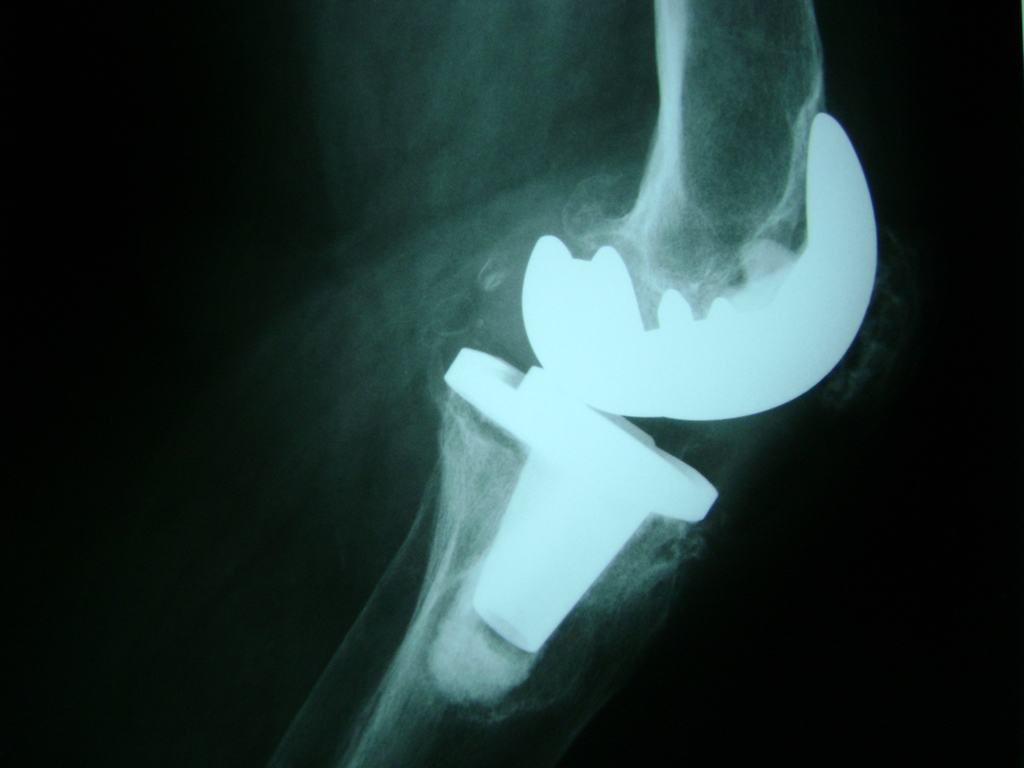

Fémur - Rodilla